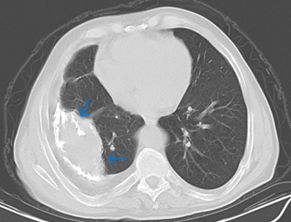

The duration of his anti-tuberculosis treatment and the specific medications he got remain unknown. He has a smoking history of 20 packs per year, has been smoke-free for 35 years, and abstains from alcohol consumption. He had hypertension and heart failure, but the patient had no history of regular drug use. He has been having frequent coughs, phlegm and shortness of breath for about 20 years. He was given oral antibiotic treatments, but when his complaints started to regress, he did not go for follow-up examinations. He used oral antibiotics 4 times in the last year, and hospitalization was recommended once, but the patient did not accept it. Looking at the patient's retrospective examinations, pleural thickening, areas containing fluid density, and calcifications were observed in the right hemithorax in the Thorax CT scans taken in 2010 and 2022 (Figures 1 & 2). In the CT scan of the patient taken in January 2024, approximately 3,5 cm was observed on the right hemithorax, which could be evaluated in favor of pleurisy sequelae (Figures 3 & 4). Sputum analysis for three Acid-resistant bacilli tests was negative. There is no elevated sedimentation, CRP, or leukocytosis.

Figure 1 Mediastinal window of March 2010 thorax CT showing a calcified pleural empyema, first CT in the patient's medical history.